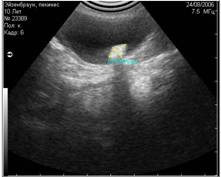

2. Дистальное затухание

При сканировании глубоко расположенных структур, получение качественного изображения затрудняется. Это связано с тем, что на глубоко расположенные структуры у ультразвукового луча остаётся мало энергии(4).

Рис. 6. Дистальное затухание. На снимке этот артефакт представлен тёмной полосой в дистальной части скана. Часто этот артефакт имитирует жидкостные структуры. |